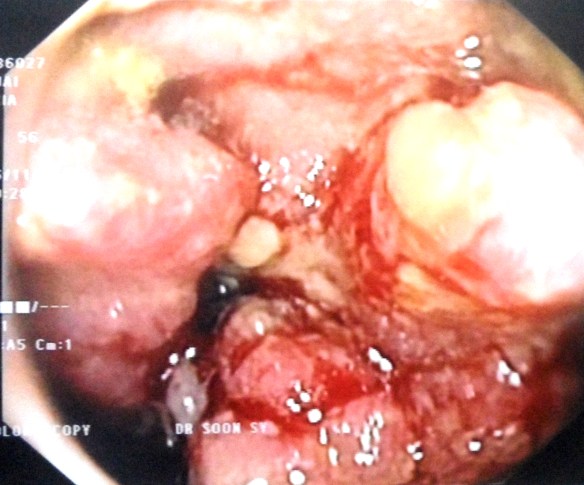

On 29 May 2018, CHK went back to the hospital again for a colonoscopy. There was a tumour in his colon and 85 percent of the passageway was blocked. A biopsy confirmed adenocarcinoma of the ascending colon.

On 26 June 2018, CHK underwent another operation (right hemicolectomy) in a private hospital in Kuala Lumpur.

The surgeon removed about 17 cm of the colon, in addition to the omentum. Unfortunately, the surgeon did not do anything to the two metastatic liver nodules.